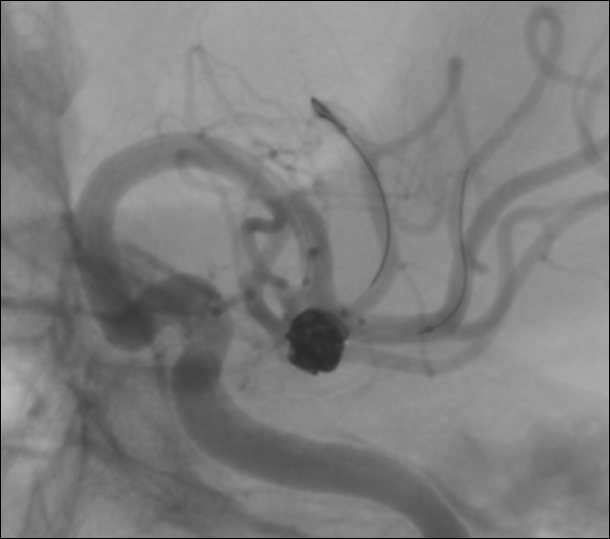

En este aneurisma se realizó la cateterización con dos balones de remodeling Eclipse 2L con microguías Traxcess y Ashahi .014, realizando dos cambios de curva para el cateterismo distal. El acceso proximal se realizó con un introductor largo Ballast .088 de 90cm que permite el uso de dos balones y un microcatéter para introducir los coils.

Con un buen posicionamiento de los balones se logró el cierre completo del aneurisma con seguridad y control garantizando la permeabilidad de las ramas. En este caso no se completó el tratamiento con stent por que la paciente debe someterse a una cirugía reciente.